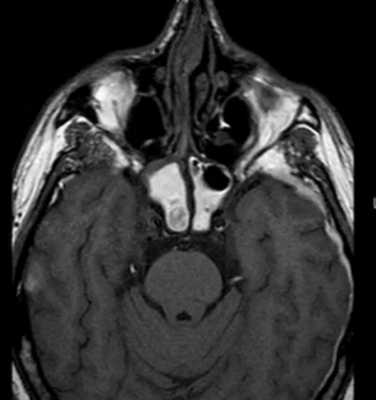

Во время КТ получают послойные снимки височной кости и окружающих тканей в трех плоскостях. Толщина среза составляет всего несколько миллиметров, что позволяет врачу-рентгенологу рассмотреть не только все анатомические образования, но и минимальные патологические изменения.

На полученных снимках хорошо видны следующие структуры:

пирамида височной кости;

ячейки и антрум сосцевидного отростка;

улитка, преддверие, передний и задний полукружный каналы;

слуховые косточки среднего уха;

стенки наружного слухового прохода;

Снимок (томограмма) височных костей в осевой проекции